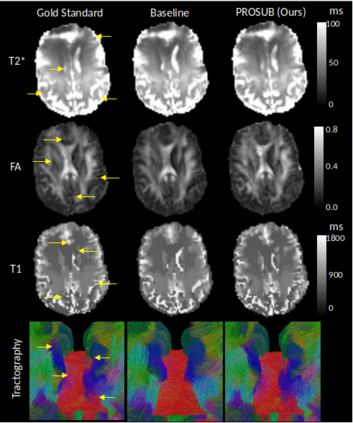

We present PROSUB: PROgressive SUBsampling, a deep learning based, automated methodology that subsamples an oversampled data set (e.g. multi-channeled 3D images) with minimal loss of information. We build upon a recent dual-network approach that won the MICCAI MUlti-DIffusion (MUDI) quantitative MRI measurement sampling-reconstruction challenge, but suffers from deep learning training instability, by subsampling with a hard decision boundary. PROSUB uses the paradigm of recursive feature elimination (RFE) and progressively subsamples measurements during deep learning training, improving optimization stability. PROSUB also integrates a neural architecture search (NAS) paradigm, allowing the network architecture hyperparameters to respond to the subsampling process. We show PROSUB outperforms the winner of the MUDI MICCAI challenge, producing large improvements >18% MSE on the MUDI challenge sub-tasks and qualitative improvements on downstream processes useful for clinical applications. We also show the benefits of incorporating NAS and analyze the effect of PROSUB's components. As our method generalizes to other problems beyond MRI measurement selection-reconstruction, our code is https://github.com/sbb-gh/PROSUB